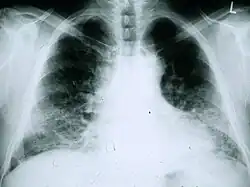

Radiologie

La radiographie du thorax est utile pour le suivi courant des patients atteints de fibrose pulmonaire idiopathique. Une radiographie classique ne permet malheureusement pas d’établir le diagnostic mais peut faire état d’un volume pulmonaire diminué, avec des atteintes interstitielles réticulaires typiques importantes près de la base des poumons[1].

L’évaluation radiologique par tomodensitométrie haute résolution est capitale dans le diagnostic de la fibrose pulmonaire idiopathique. La tomographie axiale calculée par ordinateur est réalisée à l’aide d’un scanner, sans injection d’agents de contraste. Les coupes sont très fines (1–2 mm).

La tomodensitométrie haute résolution typique en cas de fibrose pulmonaire idiopathique fait apparaître des altérations fibrotiques des deux poumons, en particulier à la base et en périphérie. Selon les recommandations conjointes de l’ATS, l’ERS, la JRS et l’ALAT de 2001, la tomodensitométrie haute résolution est une composante essentielle du diagnostic de fibrose pulmonaire idiopathique, qui permet d’identifier la pneumopathie interstitielle usuelle grâce à la présence de signes suivants à répartition typiquement basale et périphérique bien que souvent inégale[1]:

- opacités réticulaires, souvent associées à une bronchiectasie par traction ;

- réticulations intralobulaires, plus étendues que les plages de verre dépolies (ces dernières sont rares dans la FPI)

- images en rayons de miel se manifestant sous forme de cavités kystiques, en général de diamètres comparables (3–10 mm) mais souvent assez grandes, sous-pleurales et caractérisées par des parois bien définies et disposées en au moins deux rangées (La présence d’une seule rangée de kystes ne suffit pas à évoquer des nids d’abeille) ;

- la répartition est typiquement basale et périphérique bien que souvent inégale.